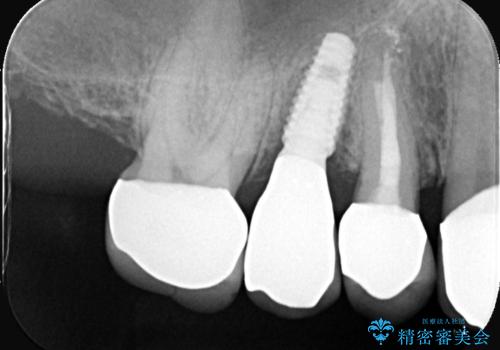

- 被せ物が外れたを主訴に来院された患者様です。

診査の結果保存困難だったので、抜歯後インプラント治療を行いました。

当院では、インプラント治療に際し、痛みの少ない治療を心がけております。

インプラント手術後、痛みが無かったことに患者様も大変驚かれ、治療にご満足いただけました。